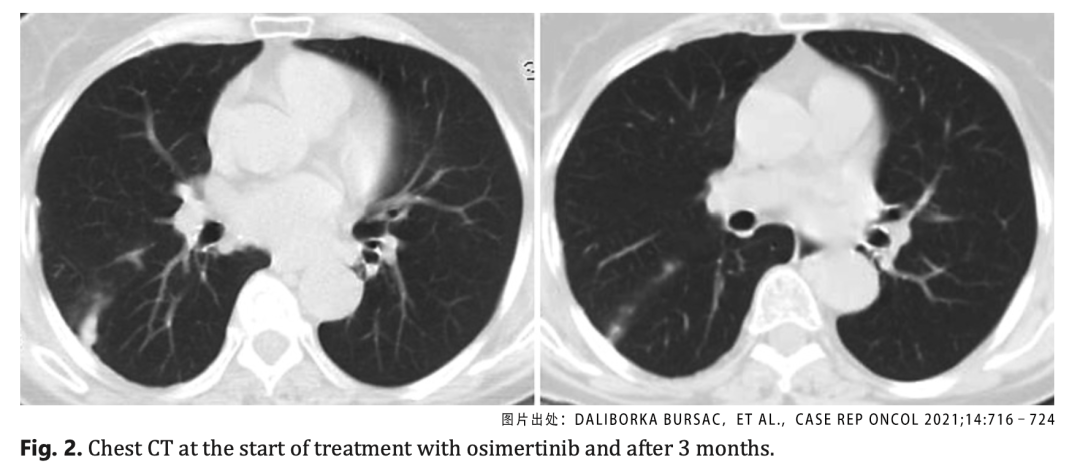

图2.奥希替尼治疗3个月后的CT检查结果

出于谨慎,患者又进行了第二次支气管镜检查,对样本进行了EGFR和ALK基因突变以及PD-L1表达水平的检测,但却都是阴性。无奈之下,患者要求进行液体活检。结果出乎意外,居然发现了EGFR基因的T790M突变,患者可以使用奥希替尼进行治疗。

在治疗三个月后复查,胸部和腹部CT显示病灶缩小,达到了临床的部分缓解。整个治疗过程脑部表现正常,目前患者仍在接受奥希替尼治疗,总治疗持续时间已经达到了59个月,也就是近5年。